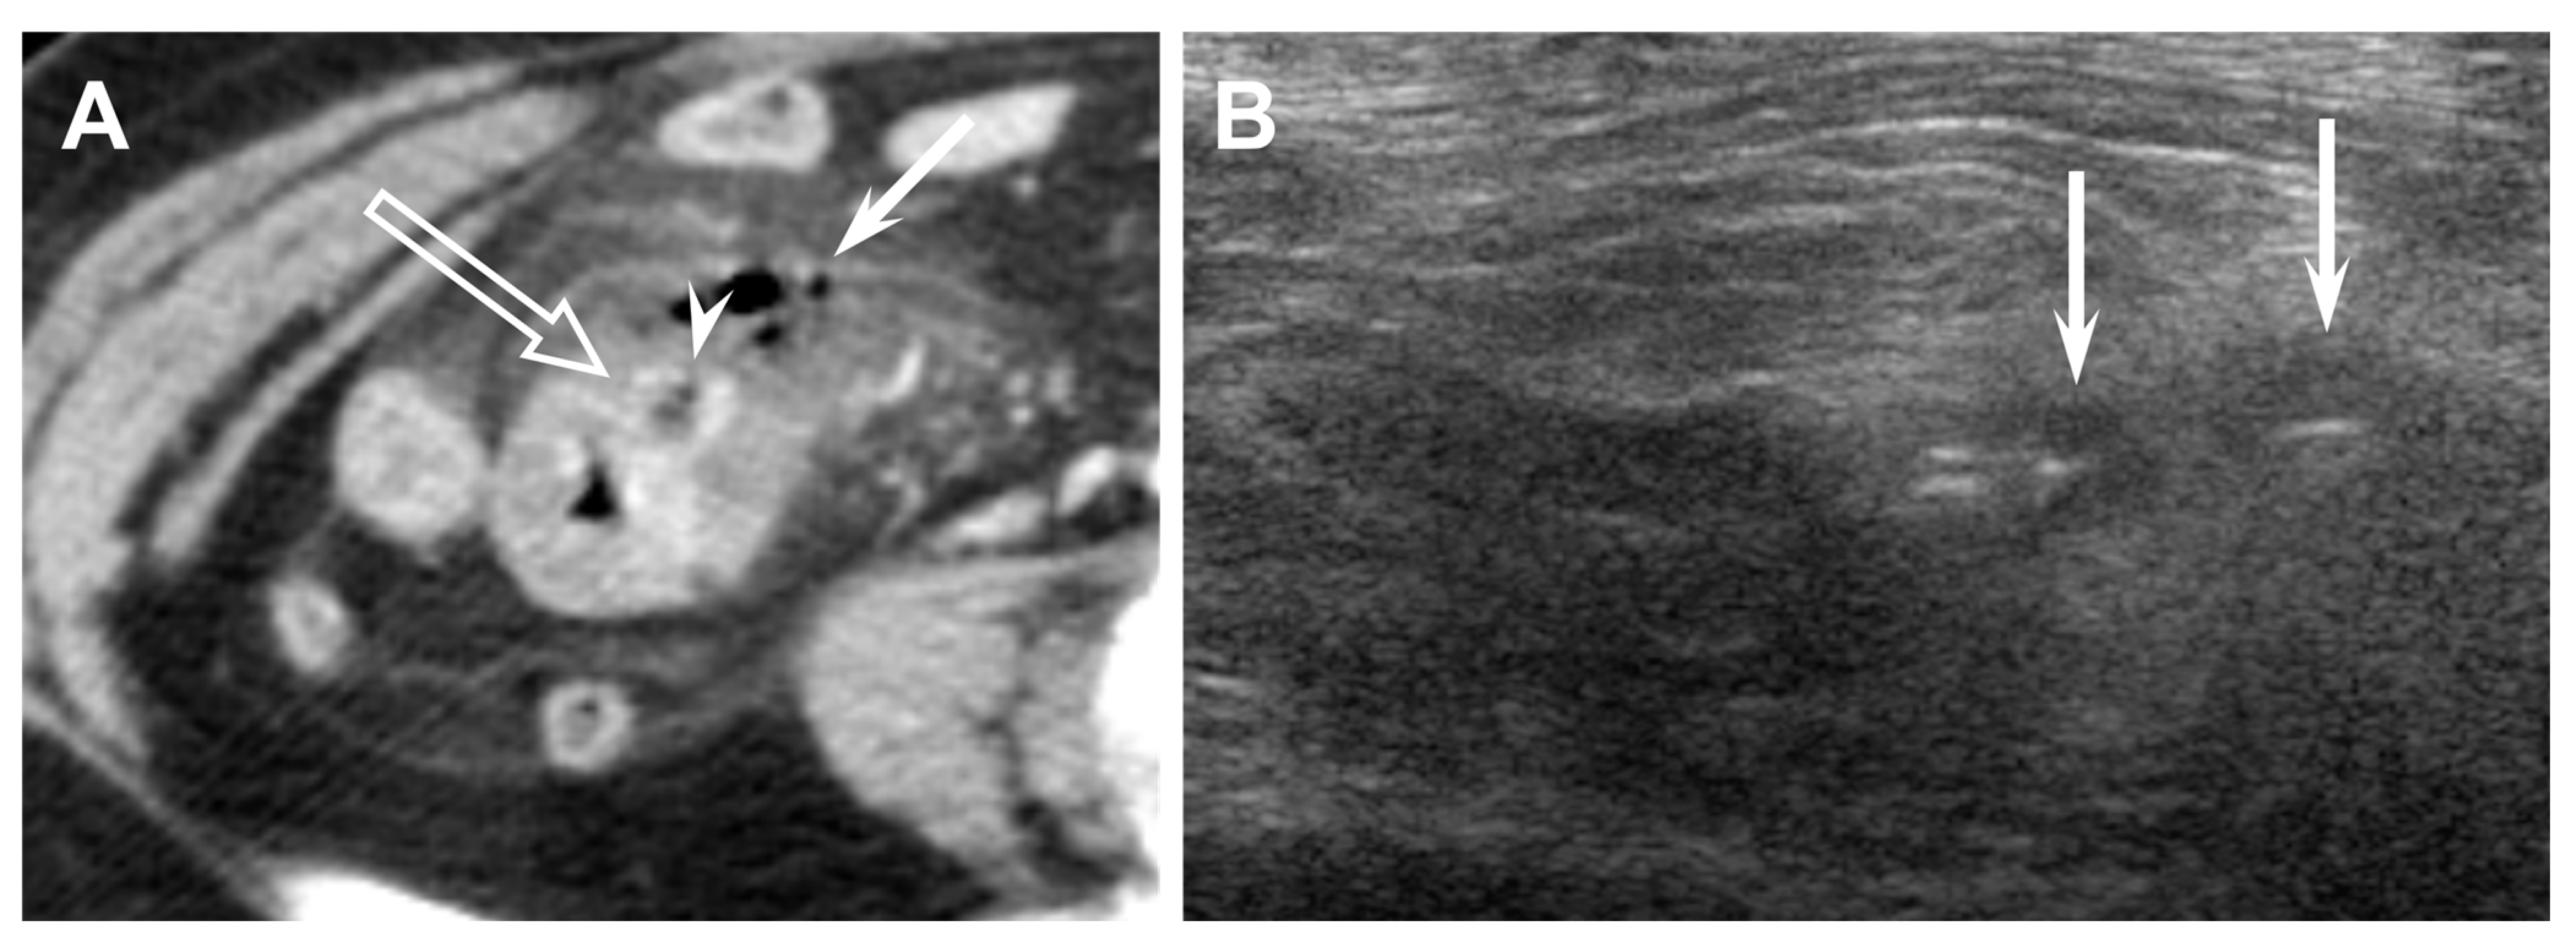

Figure 2. Sixty-seven-year-old male (patient #2) with acute perforated ileal diverticulitis. (A,B) Axial CT scans show ileal wall thickening (TI) with mesenteric abscess (A) and mesenteric fat infiltration. There is no definite inflamed diverticulum on CT. However, adjacent ileal diverticulum (arrowhead) supports the diagnosis of perforated ileal diverticulitis with abscess formation. (C) US scan with linear transducer reveals outpouching inflamed diverticulum (*) protruding from the terminal ileum (TI) and connecting to mesenteric abscess (A) with focal perforation site (arrow). (D) Barium study after 1 month shows two diverticula (arrowheads) protruding from the terminal ileum and multiple diverticula from the colon.

The CT findings for acute ileal diverticulitis are summarized in Table 2. All 17 patients had ileal diverticulum along the mesenteric border. Inflamed diverticulum was seen in 16 patients (94.1%) (Figure 1). The remaining patient did not have an inflamed diverticulum at the center of ileal wall thickening with abscess; however, adjacent ileal diverticula supported the diagnosis of acute ileal diverticulitis with perforation, and barium study after 1 month demonstrated two ileal diverticula along the mesenteric border (Figure 2). Three patients had radiodense fecalith within the inflamed diverticulum (Figure 3). All 17 patients had mesenteric fat infiltration with varying degrees and ileal wall thickening. Five patients (29.4%) were diagnosed with perforated ileal diverticulitis, which had the following findings: abscess (n = 2) (Figure 2), extraluminal fluid with air (n = 3) (Figure 4), and/or focal defect in the diverticular sac (n = 2) (Figure 5). Mesenteric venous gas (Figure 4) and mesenteric venous thrombosis were seen in two patients (11.8%), respectively.

The US findings for acute ileal diverticulitis are summarized in Table 3. All patients showed outpouching inflamed diverticular sac connecting to the ileum, peridiverticular inflamed fat presenting as hyperechoic fat around the diverticulum, and increased color flow to the diverticulum and surrounding inflamed fat on CDI (Figure 1). The inflamed diverticulum exhibited variable echogenicity (Figure 2 and Figure 3). Like CT findings, eight patients had a single diverticulum and nine patients had multiple diverticula. Unlike CT, US examinations diagnosed perforated ileal diverticulitis in seven patients. The findings indicated that five patients had both abscess and extraluminal air bubble (Figure 4 and Figure 5), one patient had only extraluminal air bubble (Figure 6), and one patient had only abscess.

Historically, acute ileal diverticulitis has been diagnosed on exploratory laparotomy for other challenging differential diagnoses [1,20]. The technological advances and widespread use of CT have enabled radiologists to play an essential role in diagnosing acute ileal diverticulitis [3,16,18]. The characteristic CT findings of acute ileal diverticulitis in this study included ileal wall thickening with small-sized inflamed diverticulum at the mesenteric side and surrounding mesenteric fat infiltration, which was consistent with CT findings in previous studies [3,4,5,6,7,8,9,10,11,13,16,18,24,30]. Especially, direct visualization of the inflamed diverticulum was the key feature in diagnosing acute ileal diverticulitis. Sixteen of 17 patients had direct visualization of inflamed diverticulum on CT. The remaining patient, who was diagnosed with perforated diverticulitis with abscess, did not show an inflamed diverticulum on CT. However, US demonstrated inflamed diverticulum protruding from the ileum and connecting with the abscess in the patient. We believe that US could play a complementary role if the inflamed diverticulum was not seen on CT.